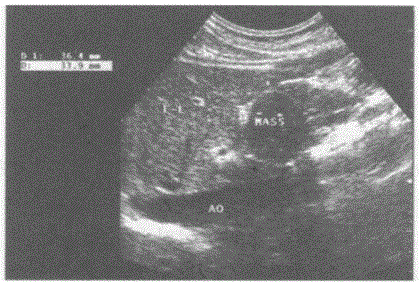

问题 临床资料:女,40岁,常规体检。 超声综合描述:腹主动脉下腔静脉前方,胰头右侧可见3.6cm×3.4cm圆形低回声区,边界清晰,包膜完整,内回声尚均匀,CDFI:内未明显血流信号,周边可见血管绕行。见下图及彩图。 {图3} 超声提示:

选项 A.腹腔肿大淋巴结 B.胰头癌 C.胰头炎性假瘤 D.腹膜后实性占位

答案 D